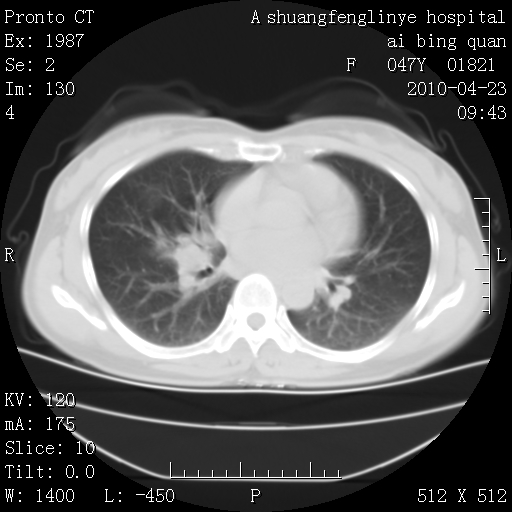

标题: CT25944:胸痛、气短、前几日高烧!肺Ca?请会诊! [打印本页]

标题: CT25944:胸痛、气短、前几日高烧!肺Ca?请会诊!

双肺多发结节,考虑转移瘤,肺癌肺转移不除外

周围型肺癌并肺转移

左侧乳腺低密度灶

双肺多发结节,部分密度较高,最大结节边缘光滑。临床有“胸痛、气短、前几日高烧”病史。首选考虑:右肺感染性病变!建议积极消炎后复查!